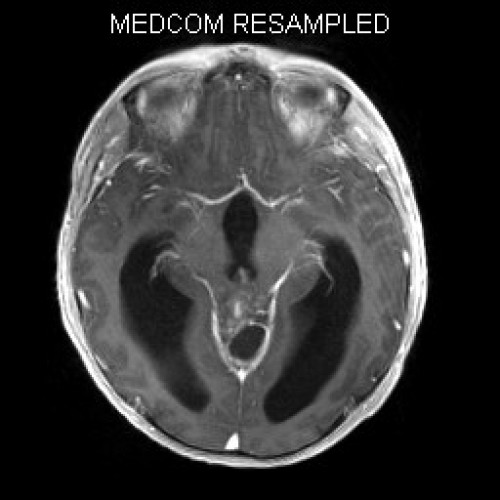

ICD: C75.3

ICD: G91.9

12-jähriger Junge. Die Eltern werden zu einem Gespräch bei der Klassenlehrerin gebeten, weil ihr Sohn sehr unaufmerksam geworden sei und seine Leistungen in der Schule bedenklich abgenommen hätten. Er droht das Klassenziel der 6. Klasse nicht zu erreichen.

Den Eltern war seit längerer Zeit bereits aufgefallen, dass sich ihr Sohn nach der Schule am liebsten ins Bett lege, um für eine Stunde einen Mittagsschlaf zu halten.